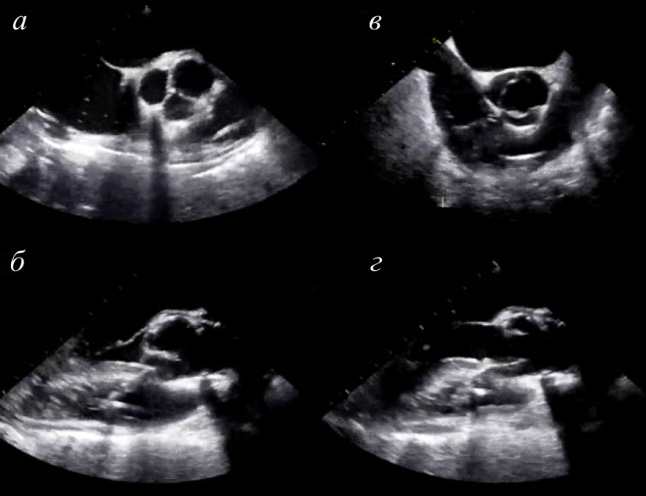

Рис. 3. Эхокардиографические снимки после операции: а и б – показывают адекватную коаптацию створок; в и г – отображают открытие неостворки клапана

В 2014 г. Озаки и соавт. [2] опубликовали результаты лечения 404 пациентов, перенесших протезирование створок АК с помощью аутоперикарда со среднеотдаленными результатами наблюдения в течение 23,7 ± 13,1 месяца. Выживаемость в группе исследования составила 87,7 % в течение 53 месяцев. В послеоперационном периоде умерли семь пациентов по причинам, не связанным с сердечной патологией. Свобода от повторной операции составила 96,2 %. Двум пациентам понадобилось репротезирование в связи с инфекционным эндокардитом (ИЭ). По данным эхокардиографии у всех пациентов в послеоперационном периоде отмечались низкие градиенты на неостворках АК (рис. 3). В исследовании участвовал 51 пациент в возрасте старше 80 лет. Исследователи не наблюдали дегенеративных изменений на неостворках АК в течение 3,5 г. [6]. В период наблюдения зафиксировано три случая летальности, не связанных с сердечной патологией. Выживаемость составила 87,0 %. Тромбоэмболических осложнений и повторных вмешательств не отмечалось. По данным эхокардиографии в течение 3,5 г. после операции сохранялись низкие показатели градиентов давления на неостворках, отсутствовала значимая регургитация на АК.